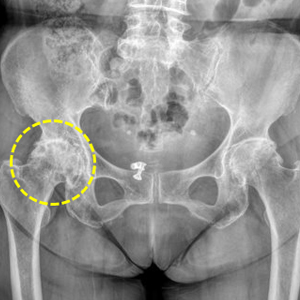

대퇴골두 무혈성 괴사 수술 전

퇴행성 고관절염 수술 전